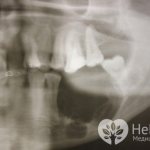

- рентгенологическое исследование, в ходе которого киста проявляется округлым очагом поражения кости с чёткими краями.

Радикулярная киста на панорамном снимке нижней челюсти в прямой и боковой проекции